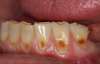

Another intrinsic factor is the patient's gastric acid entering the oral cavity. The source of intrinsic stomach acid may range from rumination or gastroesophageal reflux to chronic alcoholism, pregnancy, or vomiting caused by anorexia nervosa or bulimia nervosa.13 Figure 1 through Figure 3 show the radiographic presentation and clinical examples of dental erosion in advanced stages in the same patient caused by the combination of bulimia nervosa and chronic alcoholism.

Fig 1. Radiographic image of maxillary incisors presenting signicant radiolucency representative of enamel and dentin loss.

Figure 1

Fig 2. Facial erosion of maxillary (Fig 2) and mandibular (Fig 3) anterior teeth.

Figure 2